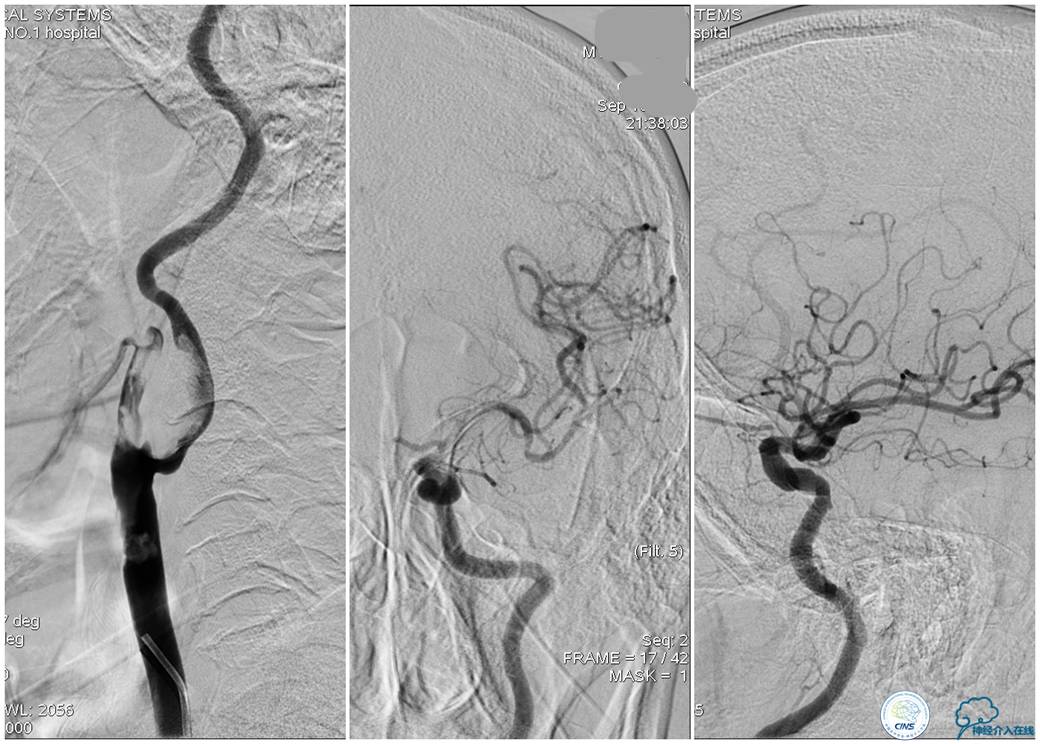

▼21:27穿刺成功,TOT 297min。左侧颈总动脉末端、颈内动脉起始部及颈外动脉起始部长条状血栓形成,随血流晃动,同侧大脑中动脉、大脑前动脉显影良好。

▼选用NAV 6 7.2 mm远端保护装置置于左侧颈内动脉C1段末端,将8F Gulding先后置于颈总动脉及颈内动脉开口部,50 ml注射器反复抽吸,抽出大量血栓。

▼颈总动脉及颈内动脉血栓抽吸完全,远端血流较前好转,TICI 3级。